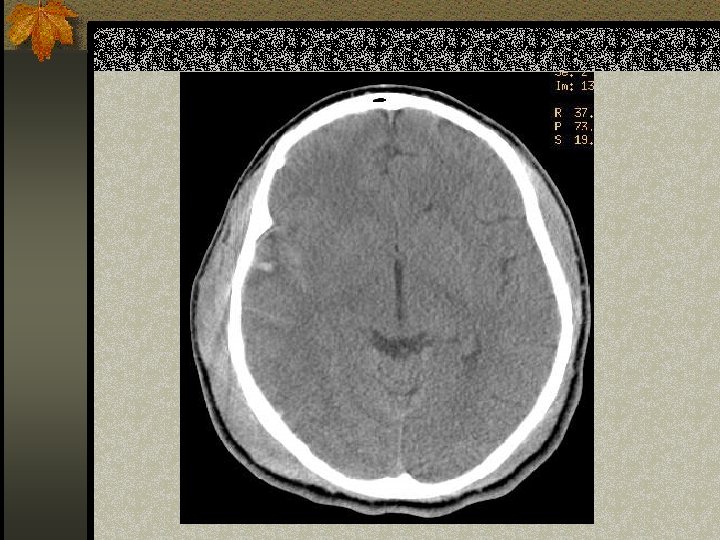

SUBDURAL HEMATOMA n Timbul antara dura dan arachnoid n Dapat melewati sutura n Timbul akibat disrupsi bridging cortical veins n Bentuk konkaf n Hipodens(hiperakut, kronis), isodens(subakut), hiperdens(akut)

W=33 L=41

PENANGANAN SDH n SDH akut dengan ketebalan > 10 mm atau pergeseran midline > 5 mm harus dievakuasi n Pasien yang koma dengan penurunan GCS >2 poin dengan SDH harus menjalani operasi evakuasi